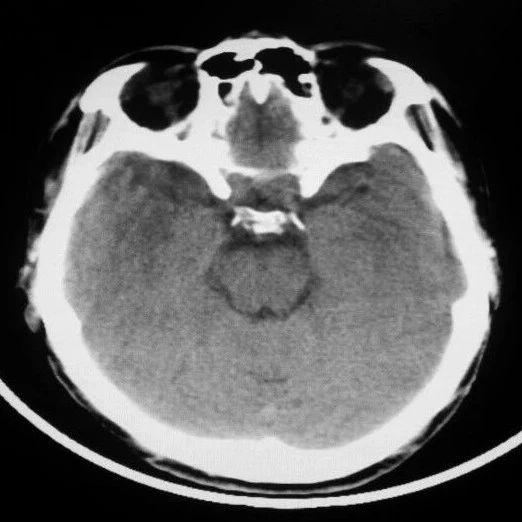

颅脑外伤的CT、MR图像诊断与鉴别诊断

颅脑外伤是一种常见的严重创伤,每年全球约有1000万人因此住院治疗。及时准确的诊断对于挽救生命和改善预后至关重要。CT和MRI作为两种主要的影像学检查方法,在颅脑外伤的诊断中发挥着不可替代的作用。

CT因其快速、便捷的特点,在急性颅脑外伤的诊断中占据主导地位。对于颅骨骨折,CT能够清晰显示骨折线,甚至可以区分线样骨折、凹陷性骨折等不同类型。在硬膜外血肿的诊断中,CT能够显示紧贴颅骨内板下方的梭形高密度影,CT值在60-80HU之间。然而,CT在显示细微结构和软组织损伤方面存在局限性。

MRI则在显示软组织结构和细微损伤方面具有优势。对于硬膜下血肿,MRI能够显示紧贴颅骨内板下方的新月形异常信号影。在弥漫性轴索损伤的诊断中,MRI能够显示脑皮髓质交界处、胼胝体等部位的异常信号灶,这是CT难以发现的。然而,MRI检查时间较长,不适合危重患者。